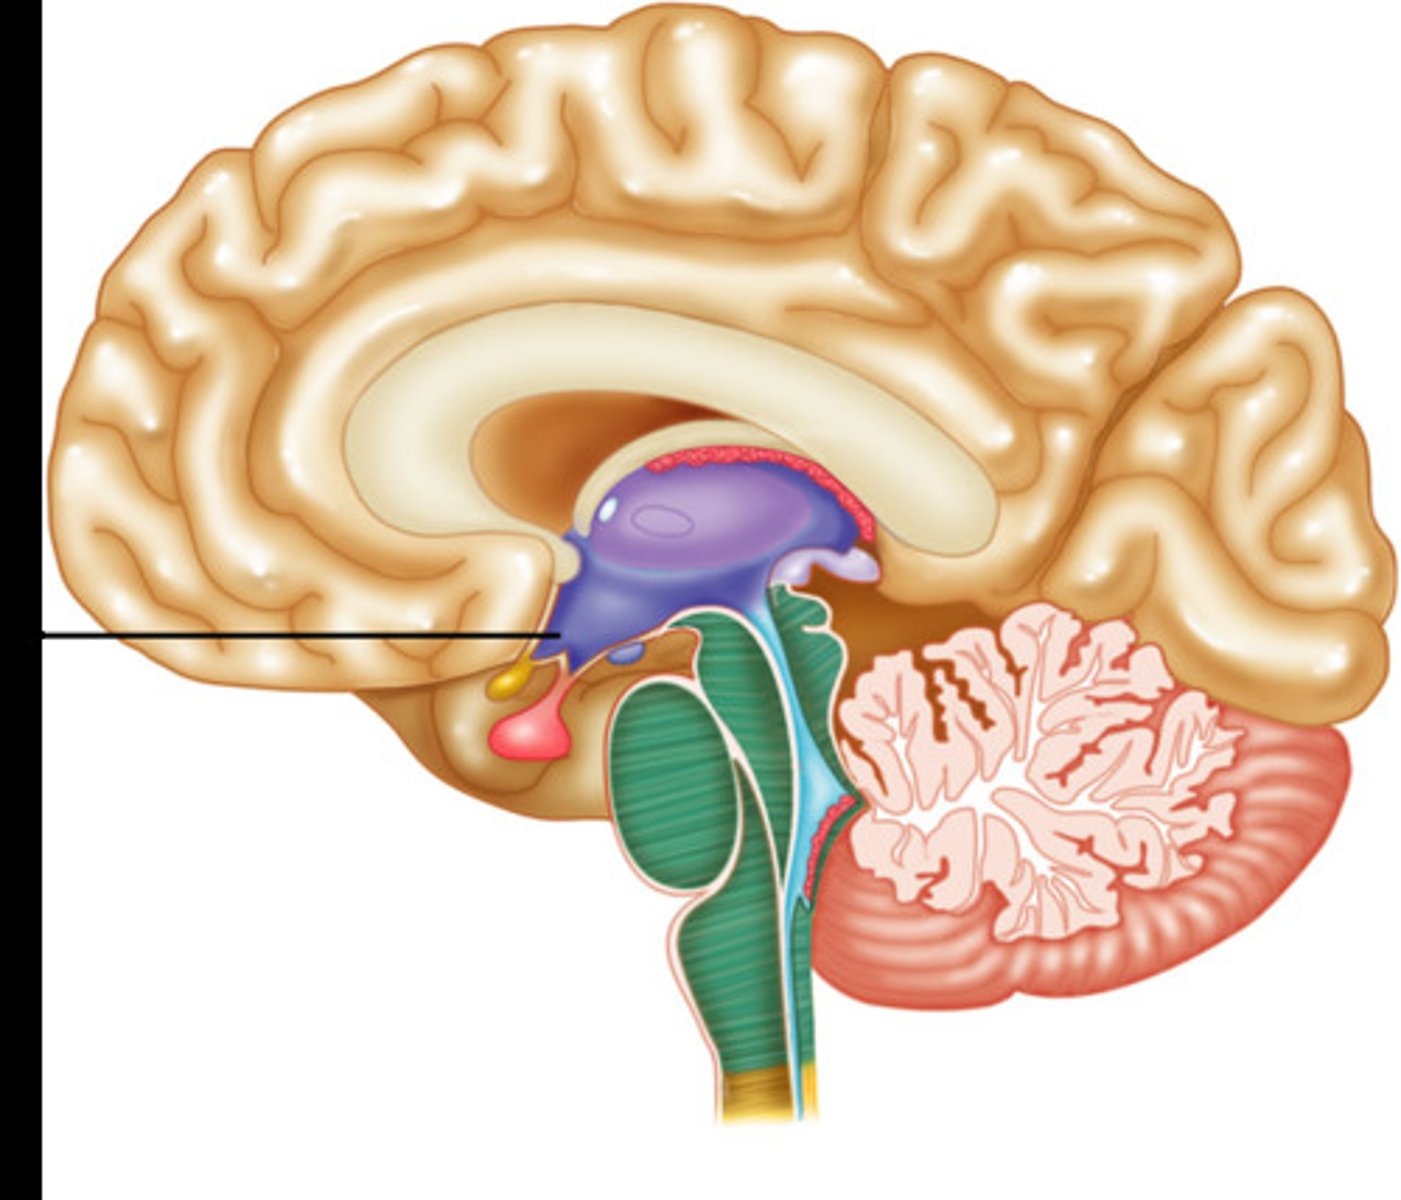

Limbic system

Part of the brain which connects different parts together and performs essential life functions

Thalmus

Part of the limbic system which recieves sensory information such as vision, touch, audio, and sends it to the appropriate lobe for processing. Think relay station

Hypothalmus

Part of the limbic system. Helps body to maintain balance and homeostasis. Controls drives such as thirst and hunger

Pituitary gland

Regulates hormones which release glands to regulate bodily function